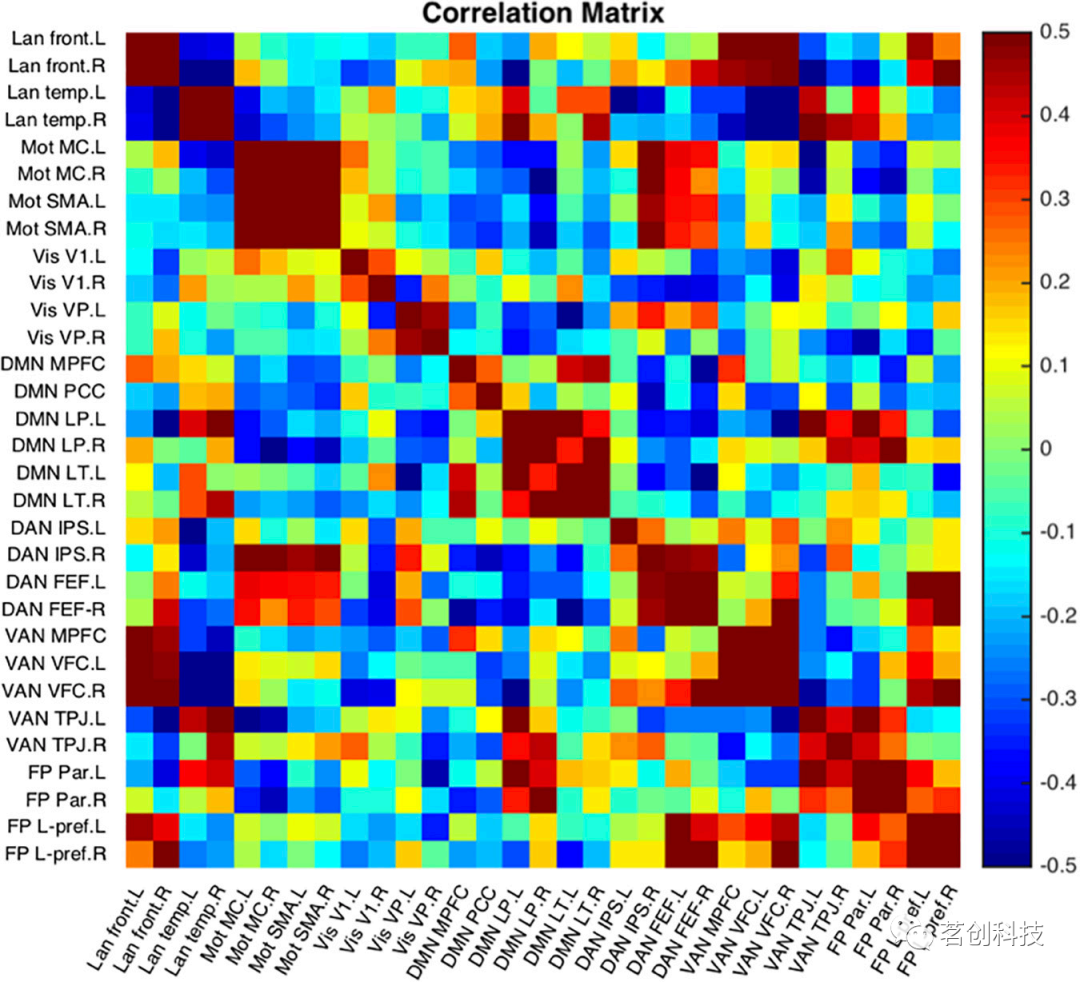

种子到种子的测量

种子到种子的数据分析提供了对所有不同种子对之间的功能连接的测量,与基于种子点的功能连接相比,种子到种子的测量显示了关于网络的更为全局的视角。NeoRS在不同的ROI之间执行Pearson相关以创建一个相关矩阵。

图12是NeoRS中包含的31个种子点的单个被试示例。

图12.种子到种子的功能连接相关性。